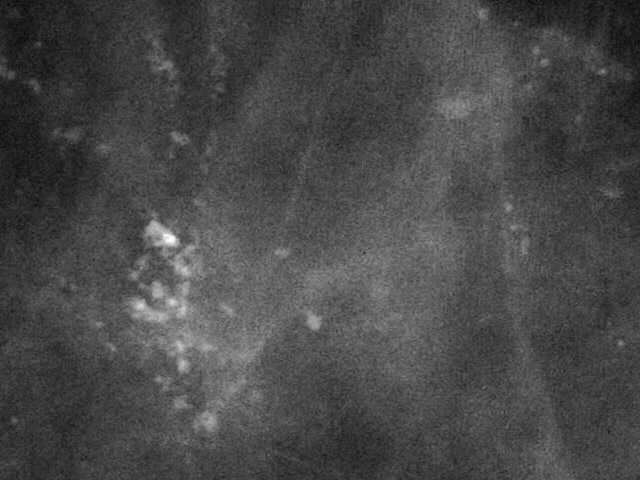

Bitte beurteilen Sie die Dignität

bösartig

gutartig